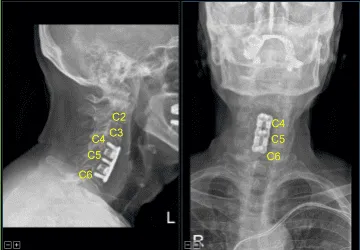

No hubo cambios significativos, por lo que se sustituyó el separador intercarrocado. Los osteófitos anteriores fueron enjuagados con un taladro eléctrico de alta velocidad. La hemostasia se obtenía con cera ósea. Se colocaba una placa lordótica de titanio de C4 a C6 y se aseguraba con un pasador.

La fluoroscopia mostró el tamaño y posicionamiento correctos, por lo que se aseguró con seis tornillos de titanio de 14 mm decorativos con un taladro eléctrico de mano de 12 mm. La apto y la fluoroscopia lateral mostraron buen posicionamiento. Todos los tornillos se apretaban finalmente usando un dispositivo integrado en la placa.

El paciente hizo un seguimiento inicial dos semanas después de la cirugía y luego continuó haciendo seguimiento en nuestra consulta de forma periódica. Durante la visita, el paciente declaró que había experimentado mejoras en su radiculopatía.